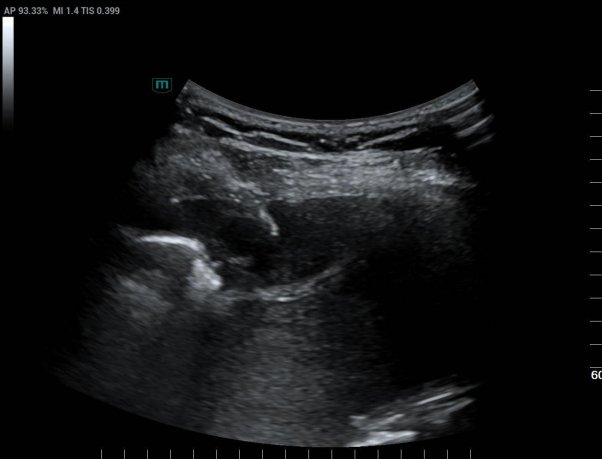

超声医学科主任潘国栋与主治医师刘金昊依据超声显示的病变范围,细致规划了穿刺点、进针路线及深度,避开了肋间动脉、神经及病变侧方的肺组织。全程在超声的实时引导下,穿刺针精准到达病变部位,采集了2条病变组织。

经超声引导下避开血管、实时显示穿刺针从进入胸膜结节到击发穿刺针的全过程

术后经病理科会诊,提示:穿刺组织呈慢性肉芽肿性炎,并见个别抗酸染色阳性的杆菌,结合分子检测结果,符合结核分枝杆菌感染。特殊染色:抗酸染色(+)。患者结核性胸膜炎诊断明确。